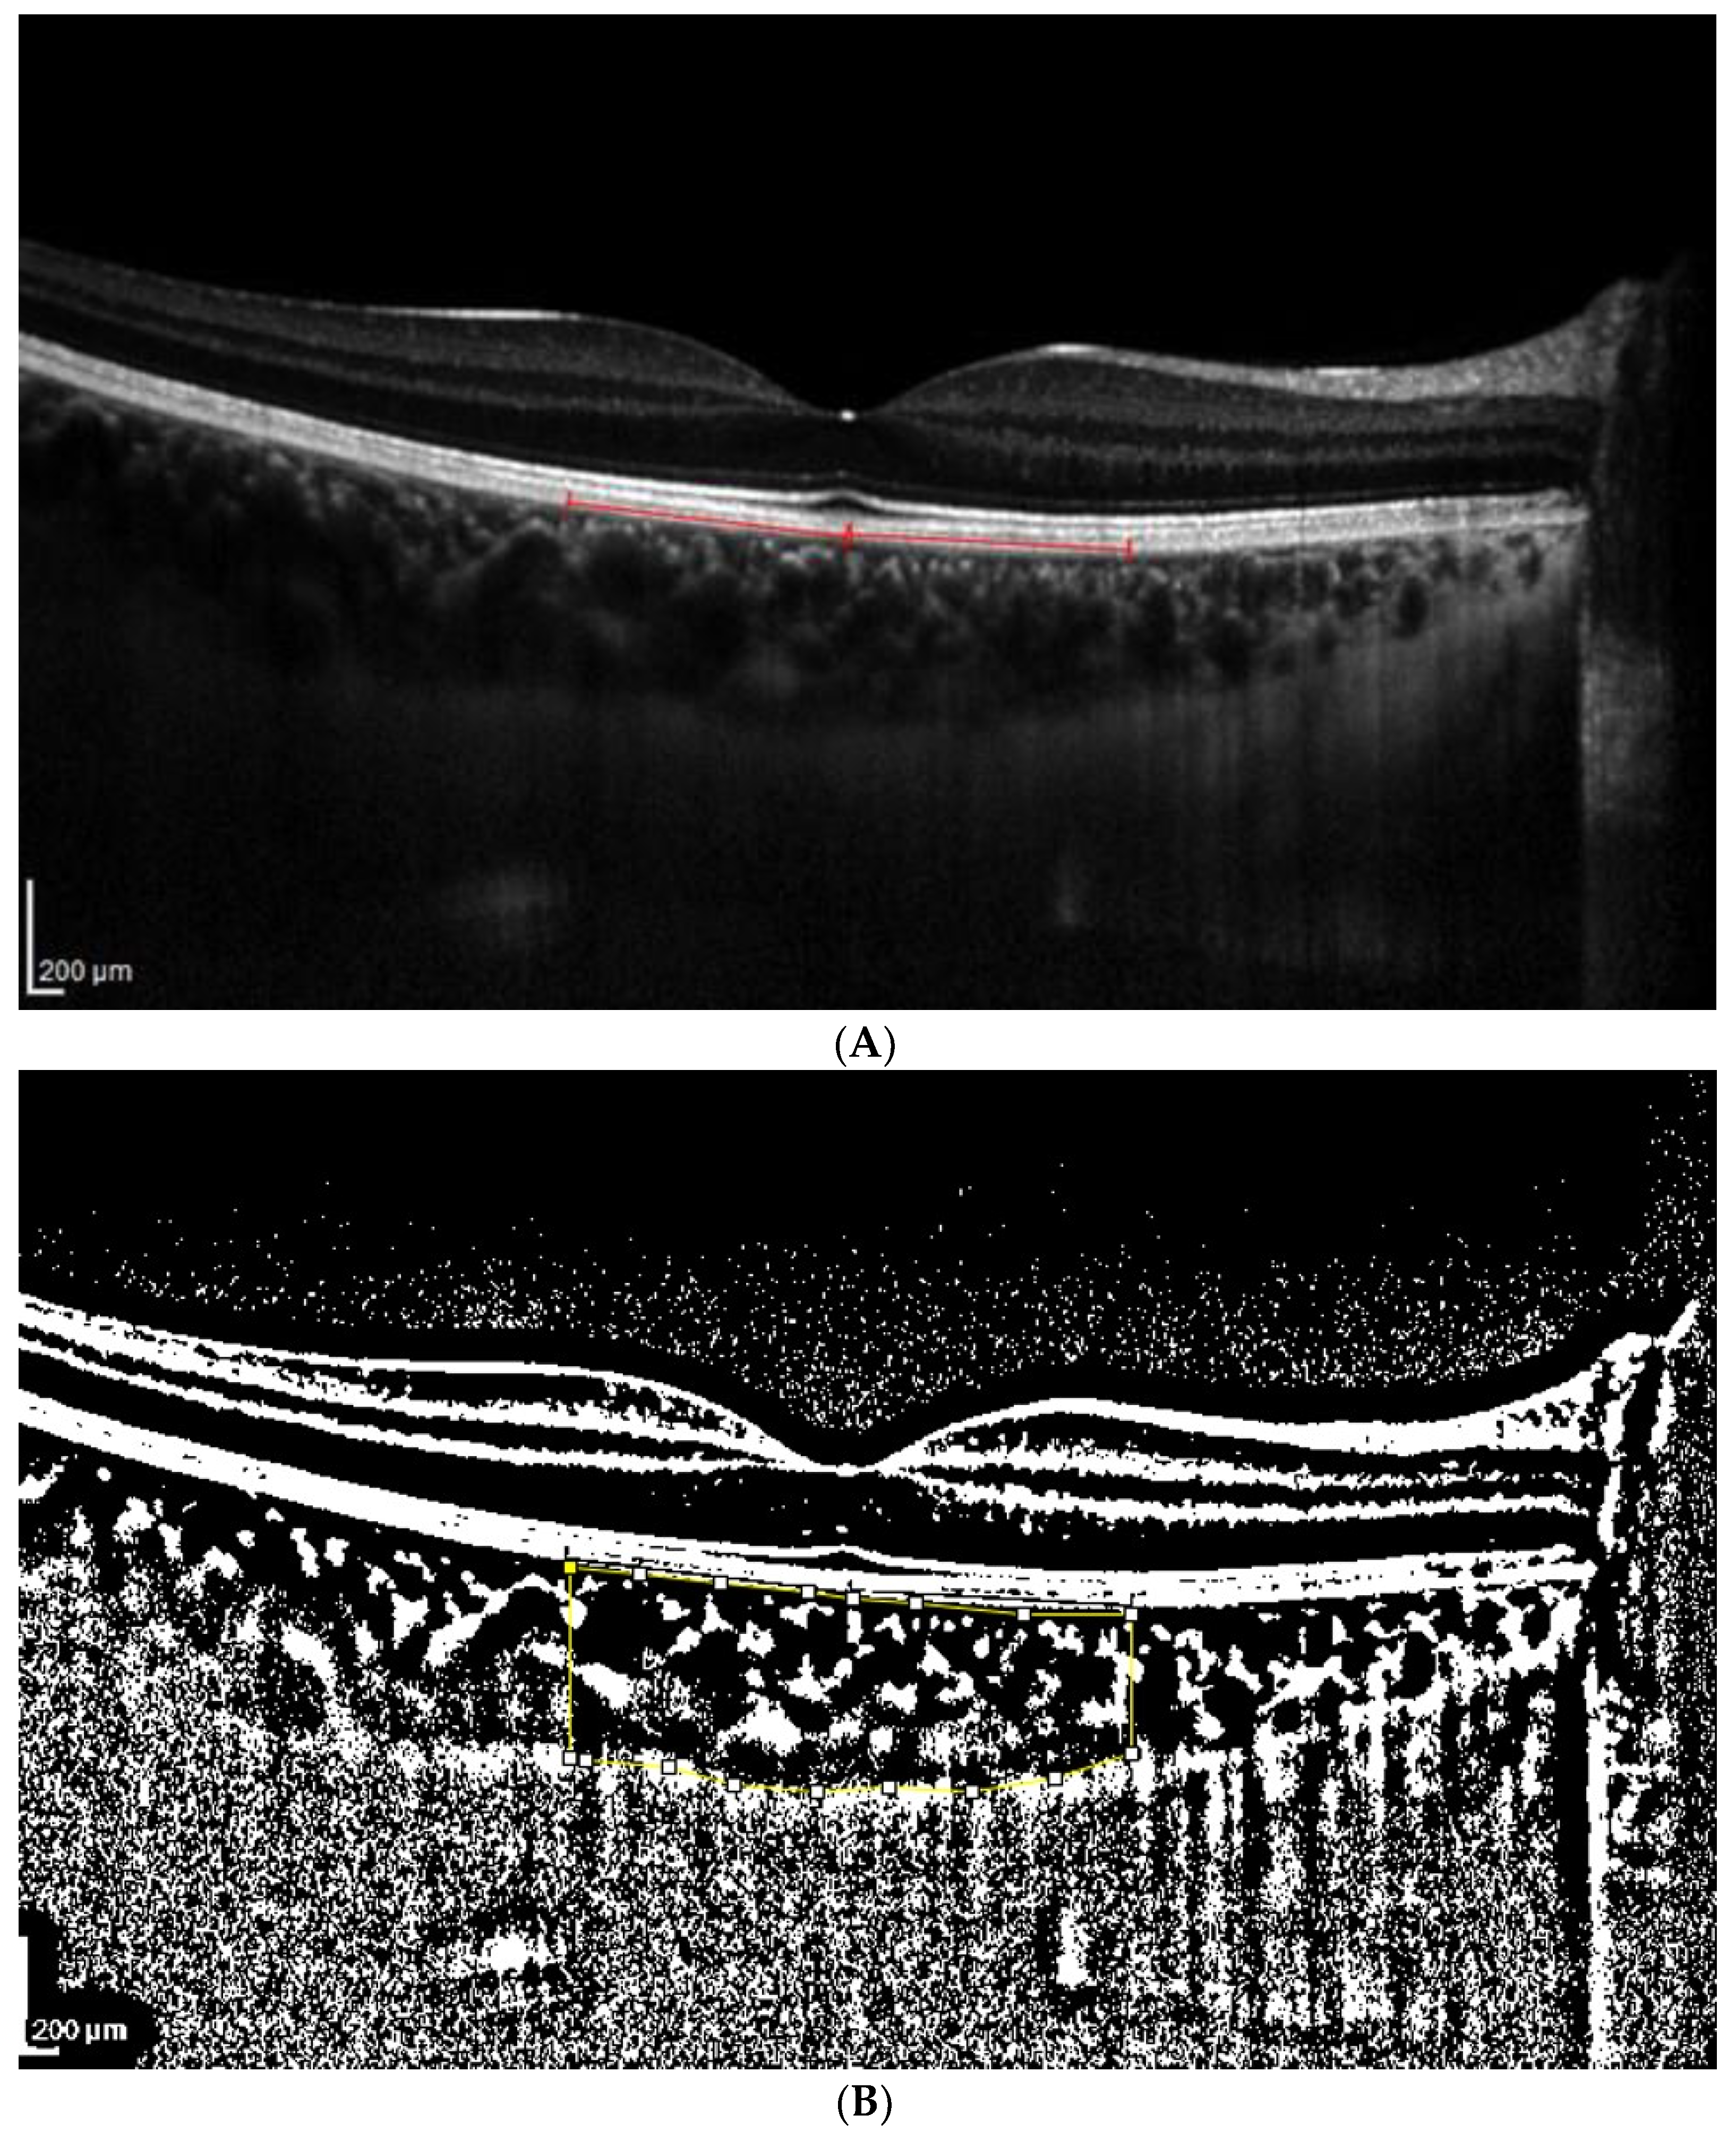

Figure 2.

(A). Patient 1 EDI-OCT right eye scan at 16 brightness. Red line indicates the RPE. (B). Patient 1 EDI-OCT right eye scan at brightness 16. Assessment of total choroidal area. (C). Patient 1 EDI-OCT right eye scan at 16 brightness. Assessment of luminal choroidal area and stromal choroidal Area. Yellow lines highlight the yellow choroidal area being calculated.